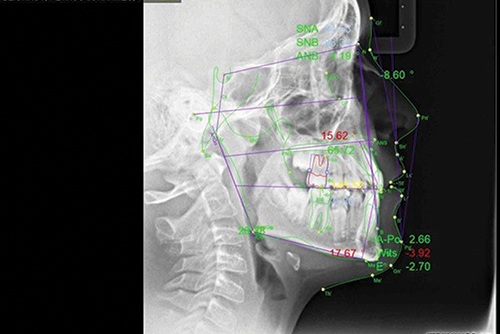

A 12-year-old boy presented with a chief complaint of “vampire teeth.” Clinical and radiographic findings revealed a complex mixed-dentition case: a mild Class III skeletal pattern with a Wits appraisal of -4 mm, a straight facial profile, and significant maxillary crowding (Figs. 1–2). The upper midline was 3 mm to the right, the maxillary canines were erupting buccally, and both lower second primary molars (75 and 85) were retained and carious. The lower left second premolar (34) was erupting under the 75, while the right ramus showed a radiolucency that raised questions about possible pathology or developmental variation. The condylar head on the right appeared atypical.

Fig. 2